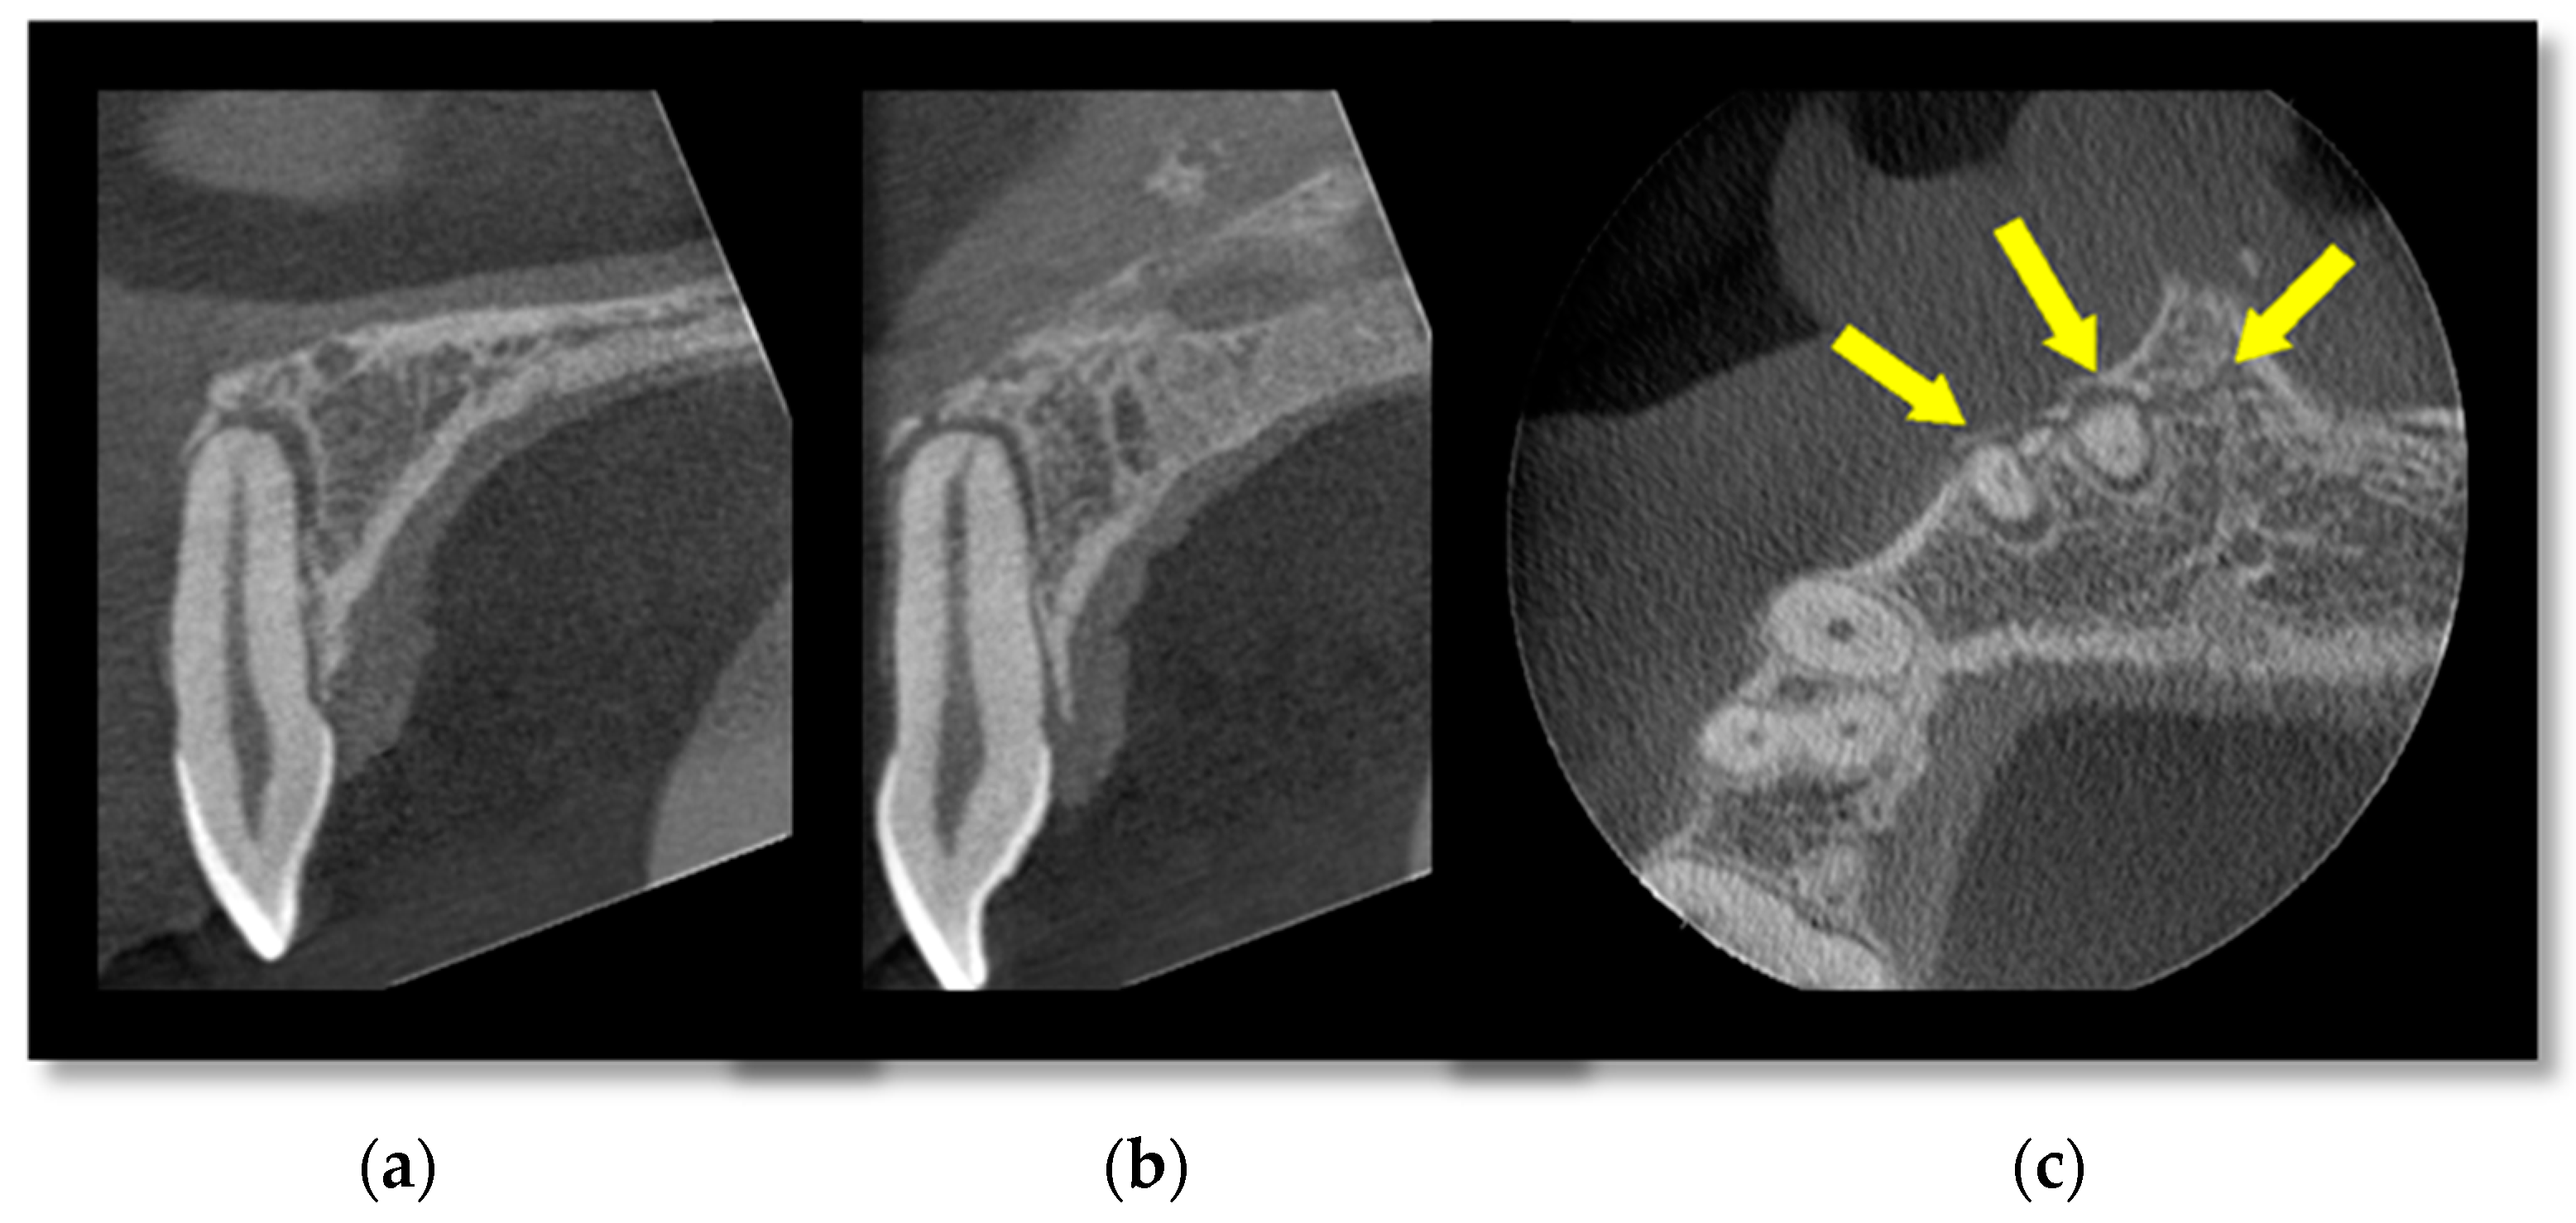

3.1. Cone Beam CT for Assessment of Dentoalveolar Fractures

- Shintaku, W.H.; Venturin, J.S.; Azevedo, B.; Noujeim, M. Applications of cone-beam computed tomography in fractures of the maxillofacial complex. Dent. Traumatol. 2009, 25, 358–366. [Google Scholar] [CrossRef] [PubMed]